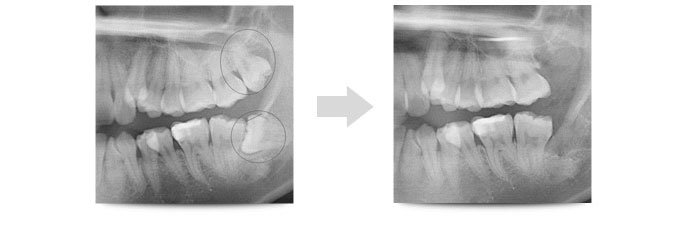

戦略的抜歯とは、親知らずの存在が、今後の中長期的視点で考えた際、問題が生じることが明白な場合は、その問題が生じる前に抜歯を行いましょうという考え方です。

例えば、親知らずが原因でブラッシングがしっかりできない部分が生じている場合。顎関節に近く、将来的に顎関節症を引き起こす可能性がある場合などなど。

一例として最近の患者さんの抜歯スケジュールをご覧ください。